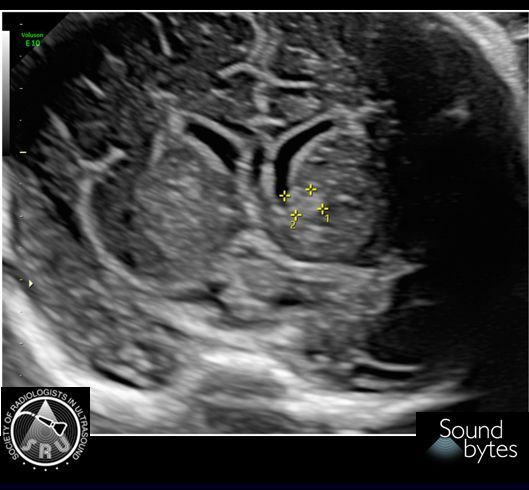

Pregnant woman presents for 2ndT anatomy scan. What's your sound diagnosis? Case courtesy of Dr. April Griffith, U of UT #RadResidents #ultrasound #RadInTraining

Answer: Size Date Mismatch Findings: Discrepancy of >7d in GA by LMP vs US late1st T (9 0/7 wk to 13 6/7 wk) suggests size-dates discrepancy, per ACOG guidelines (below). Case courtesy of Dr. April Griffith, U of UT #RadResidents #ultrasound #RadInTraining